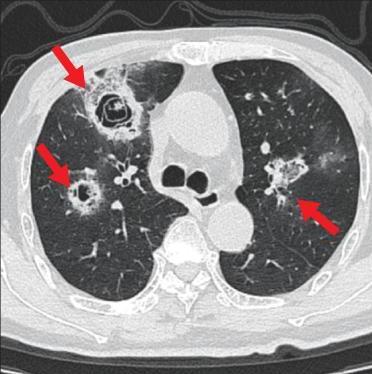

• 侵袭性肺真菌病的支气管镜表现及介入治疗效果

2025, 31(9):81-90. DOI: 10.12235/E20250317

摘要 (112) HTML (56) PDF 6.06 M (77) 评论 (0) 收藏

摘要:目的 探讨侵袭性肺真菌病(IPFD)的支气管镜表现,并评估介入治疗的安全性和疗效。方法 回顾性分析2018年5月12日-2025年5月12日于该院行支气管镜检查的35例IPFD患者的临床资料,观察IPFD的支气管镜表现及介入治疗效果。结果 共收集35例患者临床资料。其中,男22例,女13例,患者年龄(53±14)岁。基础疾病包括:血液系统恶性肿瘤10例,长期应用糖皮质激素者5例,2型糖尿病者4例,肺部恶性肿瘤2例,器官移植1例。胸部CT显示:肺部病变累及单肺叶者19例,累及多肺叶者16例。支气管镜下表现主要为:黏膜充血水肿29例(82.9%)、坏死物堵塞管腔22例(62.9%)、大量黏稠脓性分泌物17例(48.6%)、支气管部分狭窄或闭塞16例(45.7%)、黏膜坏死9例(25.7%)、黏膜出血5例(14.3%)、真菌球3例(8.6%)。其中,32例(91.4%)接受全身性抗真菌治疗,17例(48.6%)接受支气管镜局部两性霉素B灌注治疗,10例(28.6%)采用活检钳钳除病灶,6例(17.1%)采用冷冻探头冻取病灶,4例(11.4%)接受氩气刀治疗。28例(80.0%)临床症状明显改善,肺部影像学病灶缩小或消退;4例(11.4%)病灶稳定;3例(8.6%)未完成治疗。结论 IPFD多见于免疫抑制宿主,支气管镜常表现为:坏死物堵塞管腔、伴脓性分泌物、支气管管腔狭窄和局部黏膜充血水肿或坏死。全身抗真菌药物联合支气管镜下介入治疗,安全性高,且疗效好。